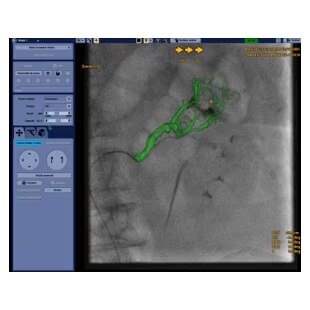

Vessel assist for peripheral

Vessel ASSIST delivers accurate and easy anatomy segmentation and accurate vessel quantification from 3D volumes. It also offers advanced 3D roadmap and augmented image guidance capabilities to guide catheter with confidence.

Plan

Automatically extract the bone and vessel anatomies. Edit vessel centerlines and bridge them through occlusions.

Select from the sub-volumes of vessels, centerlines, calcifications and landmarks to overlay on live fluoroscopy for 3D fusion guidance, with digital zoom, to guide recanalization.